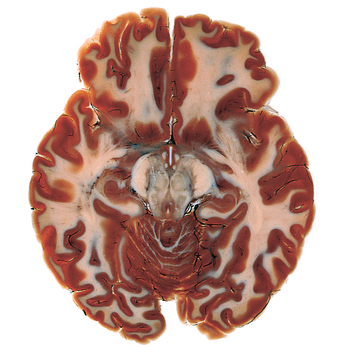

The process of plastinations follows the idea that if you inject a body with plastic to coat the cells then it will be preserved in its original state - this follows the same idea as coating the outside in a thick layer of plastic but allows the detail of the organ to be seen for what it is and in closer detail. I find these works hugely interesting and enlightening and has really allowed me to see the shape and textures of the muscle and nerve tissues. I dislike the fact that the pieces are stationary because as biological organisms we are continually moving and changing whereas here they have only captured one point in time, therefore a lot of work is needed in order to understand a biological sequence such as an electric impulse. This makes a lot of Dr. Hagens work redundant for my own use. Even though this may be the case the works ( like the plastinated brain) have provided a solid understanding of if shape and use - this is something that is essential to my work and without wich I could not proceed. I hope to meet similar standards of work in my project - including things like biological accuracy and aesthetic and natural symmetry (not quite exact). Looking at these bodies has pushed me to work with real organs and to study them fully.

The organs such as the brain and heart are more accurately portrayed when preserved with the method of plastination. This is because it retains the detail of each tissue while also keeping its three dimensional shape. This has shown its importance as when resin is used for the same purpose the original organ can not be touched. Plasination allows the original organ to show in its full glory meaning that it can actually be touched and held a very important part of learning and understanding.

Above an image shows where the nerves are most on the body - the more nerves the larger the image. This shows that they are most predominantly placed in areas which we use incredibly regularly, mostly in our face and fingers. The image to the right, however, shows a real central nervous system made up of the brain and the spinal chord. all the nerves in our bodies end up here. This idea reminds of a 'collecting duct' where the many electrical impulses occur this is a huge element to how we survive as it controls all our actions, reactions, reflexes and even our balance. It is this idea that I want to create and visualise in my work looking at this organ and showing it as a column of electricity. I particularly like the shape and find that it is very similar of that of an electric circuit board the nerves peeling off like wires from the main frame. The very bottom is particularly pleasing as it continues to follow the pattern while slowly widening and phasing out - it is a shape that I want to work with and include in my project. The only frustrating thing when using this as a referance is the fact the 'myelin sheeth' - a protective fatty layer - still surrounds the nerves like a skin which means that they are partially blocked and can not be seen en their entiartiy, this is not something that I wish to include in my work.